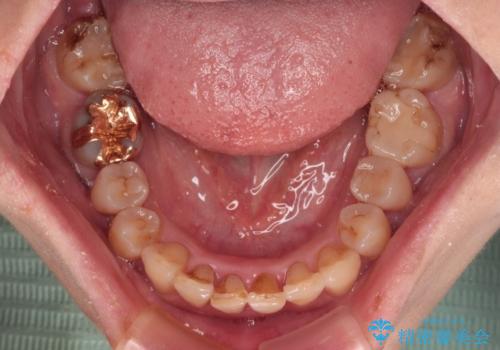

ディープバイトと前歯のデコボコ インビザラインによる矯正治療

- 前歯のディープバイトと叢生を気にして来院された患者様です。

下顎大臼歯が手前に倒れていたため、起き上がらせることで咬み合わせ高さを挙上し、ディープバイトと叢生を改善することとしました。

インビザライン特有の奥歯の噛みにくさが治療後半に発言しましたが、無事に終了させることができました。